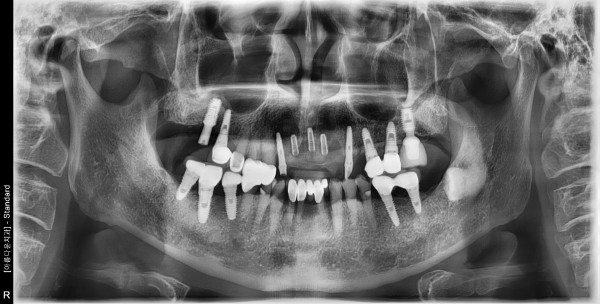

70대 남성 임플란트 식립

2d74e31fb819137f530da93a17333eb6_1759282